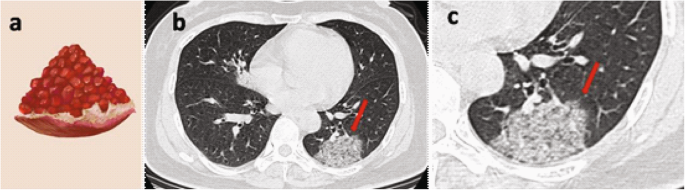

A older female patient experiencing fever and cough for 1 day,,and who had 3 days of travel history in the epidemic area before onset. a Pomegranate hand painting. b Non-contrast enhanced chest CT scan shows that the GGO in the posterior basal segment of the left lower lobe and vascular thickening, bronchiectasis, and interlobular septal thickening, showing a “pomegranate sign” (red arrow). c A partially enlarged image at the same level as in figure b, suggesting that the GGO in the posterior basal segment of the left lower lobe showed a “pomegranate sign” (red arrow)

In this study, nine patients (26.1%) presented with “pomegranate sign”, which is an atypical chest CT feature of COVID-19. A “pomegranate sign” can be characterized as a further increase of the range of ground-glass opacity that occupies part of the lung sub-segment, the more significant thickening of the interlobular septum, complicated with a small amount of punctate alveolar hemorrhage [9, 12], and lesions that are in imbricate arrangement, and are similar to a pomegranate. Moreover, among seven patients (20.6%) who developed a “rime sign”, two were critically ill. A “rime sign” is characterized by numerous alveolar edemas. Hemorrhagic necrosis can be observed in some alveoli. Moreover, mucus and hemorrhagic exudate diffusely cover the bronchiole wall. Microscopically, the wall thickening, small vascular proliferation, luminal stenosis, and occlusion, accompanied by interstitial infiltration of inflammatory cells, such as lymphocytes, plasma cells, and monocytes [12], as well as numerous pulmonary interstitial fibrosis and partial hyaline degeneration are observed. This type of lesion has a wide range and looks like a white rime attached to abranch.